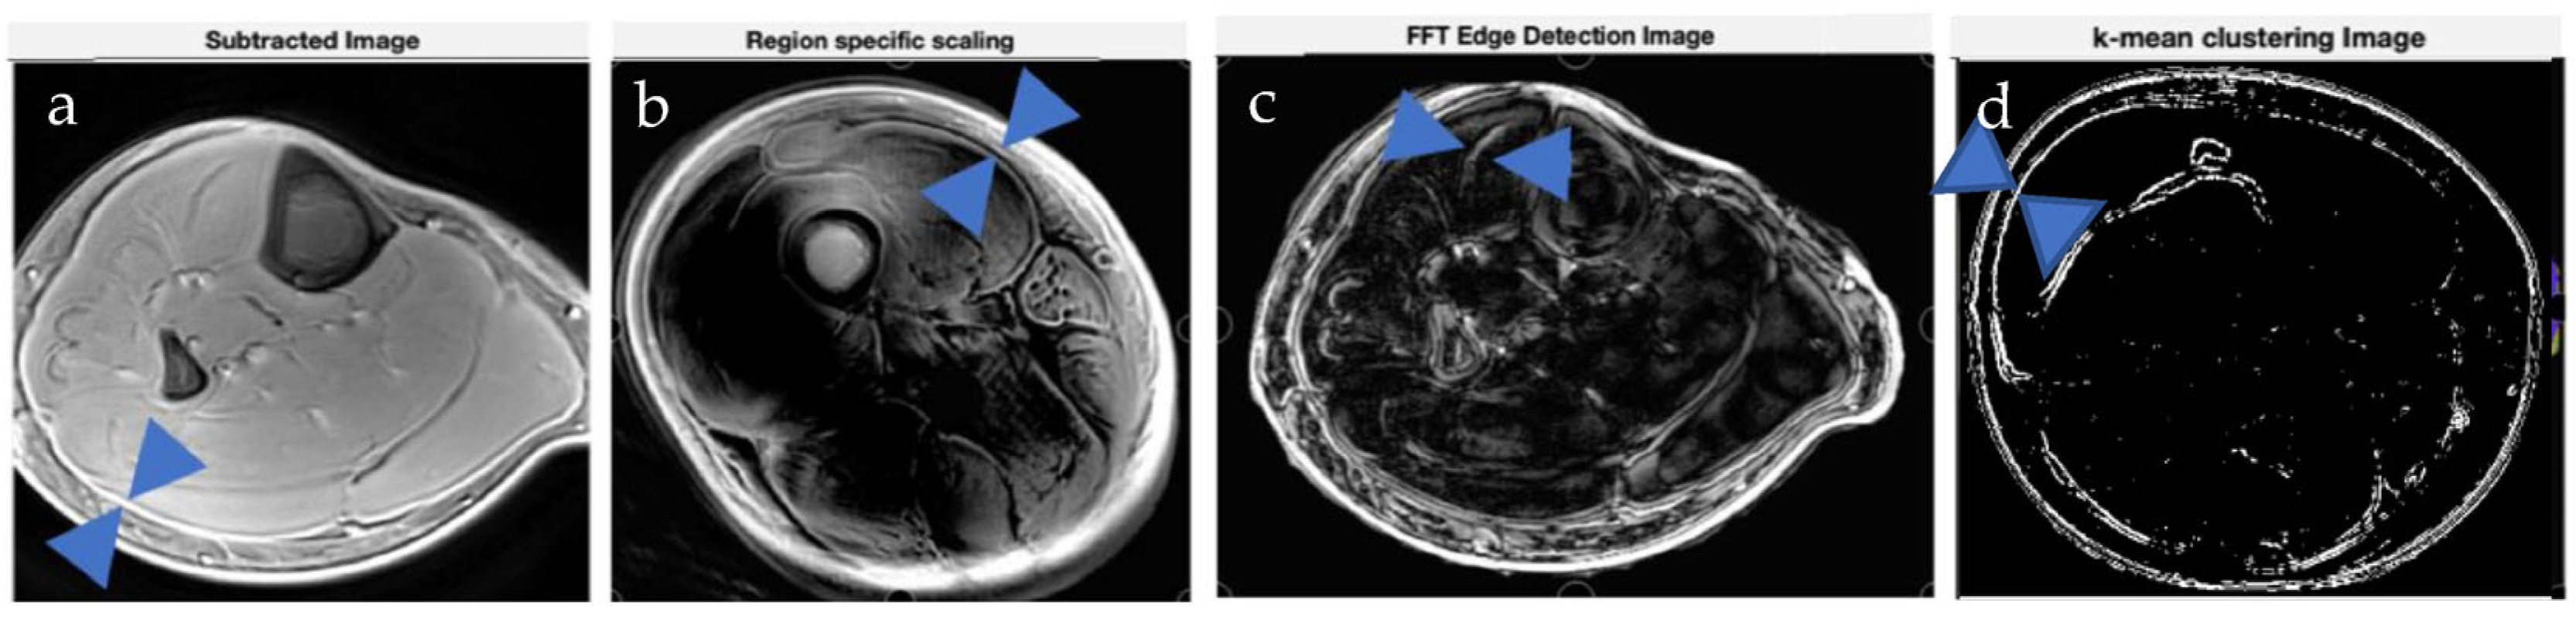

2.2. Image Processing Pipeline

2.2.1. Pipeline of Operations Used in This Section

2.2.2. Region-Specific Scaling

2.2.3. Other Preprocessing Techniques

2.2.4. Edge Detection Method Using FFT

2.2.5. K-Means Clustering

3.2. Image Processing Method Results